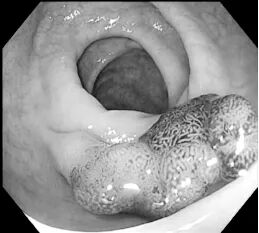

劉姨到了醫(yī)院后,消化內(nèi)鏡中心主任徐永輝馬上開通綠色通道為她進(jìn)行腸鏡檢查,發(fā)現(xiàn)腸道有多個(gè)息肉,其中最大的約有2cm。在征得患者同意后,徐永輝主任成功為其施行腸鏡下病變粘膜切除術(shù)(EMR)。術(shù)后,患者恢復(fù)情況良好,病理結(jié)果提示結(jié)腸管狀腺瘤伴低級別上皮內(nèi)瘤變。

劉姨腸道發(fā)現(xiàn)的巨大息肉